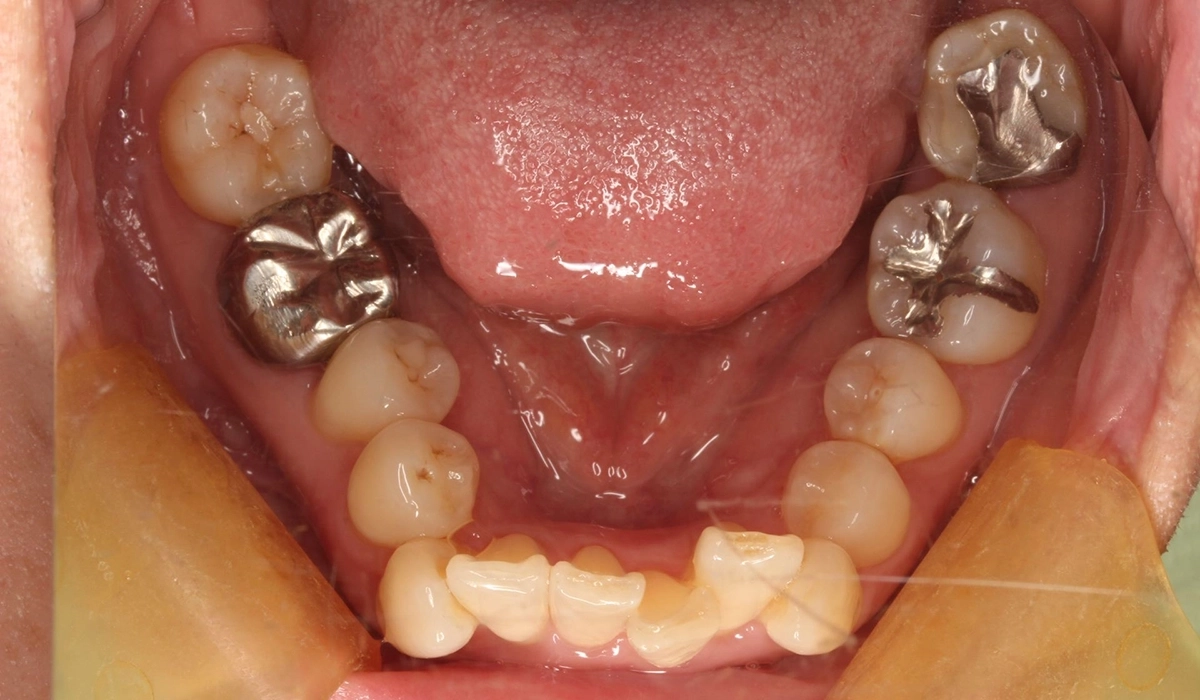

術前:上顎

術前:下顎